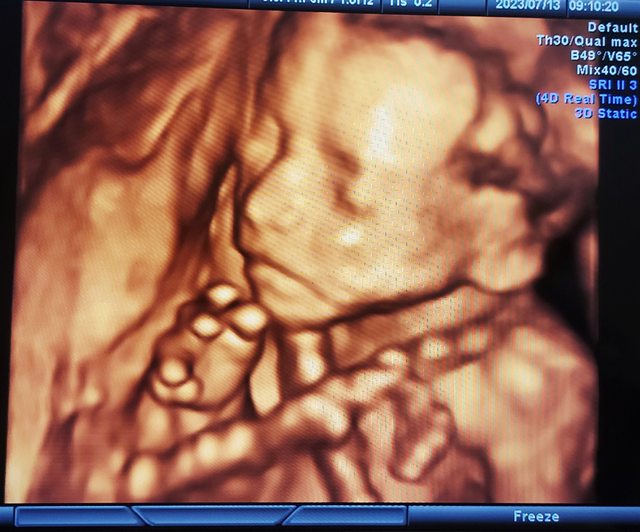

: 附上一張寶寶高層次的帥照,

: 希望他可以平安的來到媽媽身邊陪伴我們